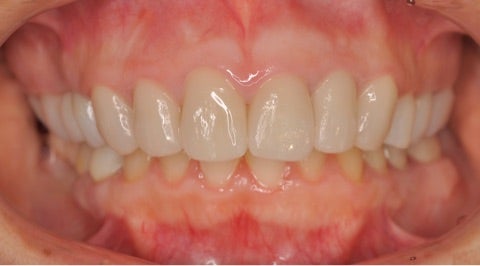

<治療後>

▶︎患者様のご希望により、全体的な見た目の改善と審美性の追求を行いました。

上顎の歯には全てジルコニアセラミッククラウンプレミアム¥220,000-/本

を使用し、《写真左下にはインプラントを2本埋入》しています。

ディープバイトの改善のため、スプリントを使用し、1mmのバイトアップも図っています。

▶︎奥歯のクラウンの高さが上がり、顎関節にも影響がないことを確認し、